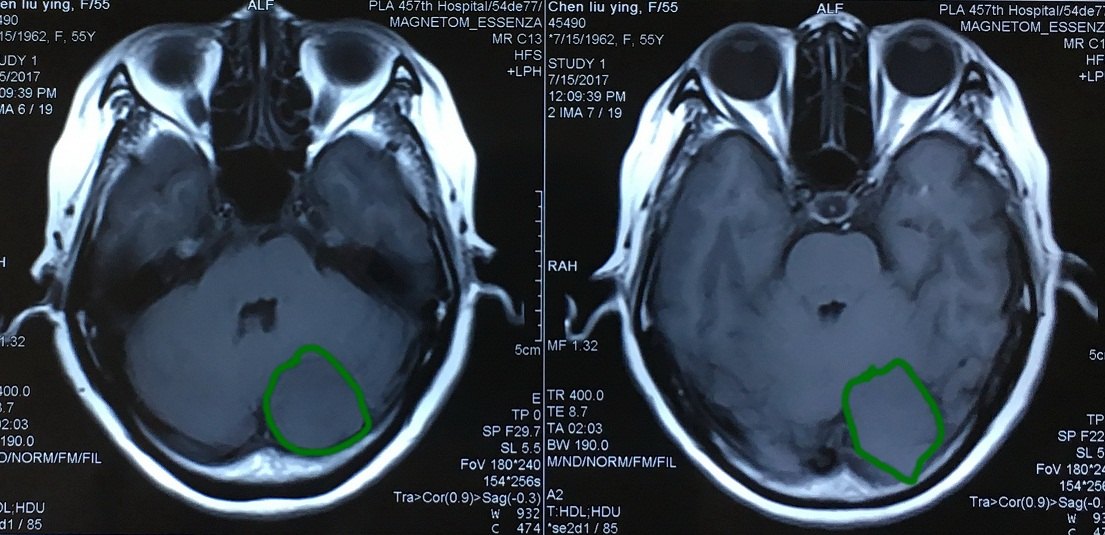

横窦天幕脑膜瘤手术一例 - 微医(挂号网)

图片尺寸1260x578